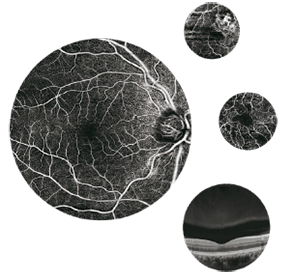

- OCT

- Retinógrafos

- Microperímetros